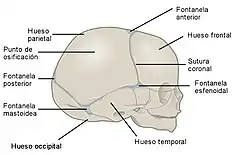

Cráneo de un recién nacido. Son visibles las suturas entre los huesos del cráneo que corresponden a una articulación de tipo sinartrosis con nula movilidad. | ||

Las funciones más importantes de las articulaciones son constituir puntos de unión entre los componentes del sistema óseo (hueso, cartílagos), y facilitar movimientos mecánicos, proporcionándole elasticidad y plasticidad al cuerpo. Algunas articulaciones no son móviles, como las que se establecen entre los huesos del cráneo, sin embargo son de gran importancia pues permiten la protección del encéfalo y hacen posible al mismo tiempo su crecimiento durante la infancia.

Fibrosas

Son aquellas en que los extremos de los huesos están unidos por tejido fibroso. Este tipo de articulaciones tienen muy poca movilidad. Un ejemplo de articulación fibrosa son las suturas que unen los huesos del cráneo. Un tipo particular de articulación fibrosa es la sindesmosis en la que dos huesos se unen mediante una lámina de tejido fibroso, como ocurre en la membrana interósea del antebrazo que une el cúbito con el radio. Un caso particular es la sindesmosis dentoalveolar, también llamada gonfosis, que es una articulación fibrosa, sin movimiento en condiciones normales, que se establece entre la raíz de una pieza dental y la apófisis alveolar situada en la mandíbula.[7]

Sinartrosis

Las sinartrosis son articulaciones que tienen muy poca movilidad. Las uniones entre los huesos que forman el cráneo se llaman suturas y son un buen ejemplo de sinartrosis.[9] Dependiendo del tipo de tejido que sirve de unión, se dividen en:

- Sincondrosis, cuando el tejido de unión es cartilaginoso. La articulación costoesternal entre la primera costilla y el esternón es un ejemplo de sincondrosis. También se consideran sincondrosis las placas de cartílago que se encuentran en las metáfisis de los huesos largos durante la infancia y permiten el crecimiento longitudinal del hueso, este tipo de sincondrosis no tiene función alguna de movimiento, cuando el cartílago se osifica totalmente y finaliza el proceso de crecimiento longitudinal del hueso, la sincondrosis se transforma en sinostosis.

- Sinfibrosis, cuando el tejido de unión es fibroso como en las suturas entre los huesos del cráneo.